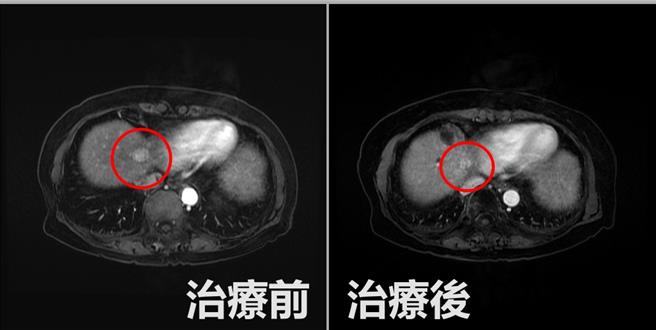

直到今年初,阿嬤回診時安排超音波檢查,發現在肝臟、心臟交界處新長出1顆2公分大的肝臟腫瘤,幾乎是貼在心臟邊緣處,由於腫瘤位置太過刁鑽,加上患者年紀大,採手術切除術有肝衰竭的風險,如用電燒,有可能傷及心臟引發更嚴重的併發症。

陳政國與家人討論評估後,決定採取緩和方案,先是動脈栓塞治療,利用極細的導管將拴塞物從股動脈一路延伸到肝動脈,藉此堵住供應肝腫瘤血液的血管,讓腫瘤缺血壞死或縮小,之後再搭配放射治療逐漸殺死癌細胞,歷經長達1年、4次完整療程後,順利將癌細胞清除完畢,讓阿嬤放下心中大石。